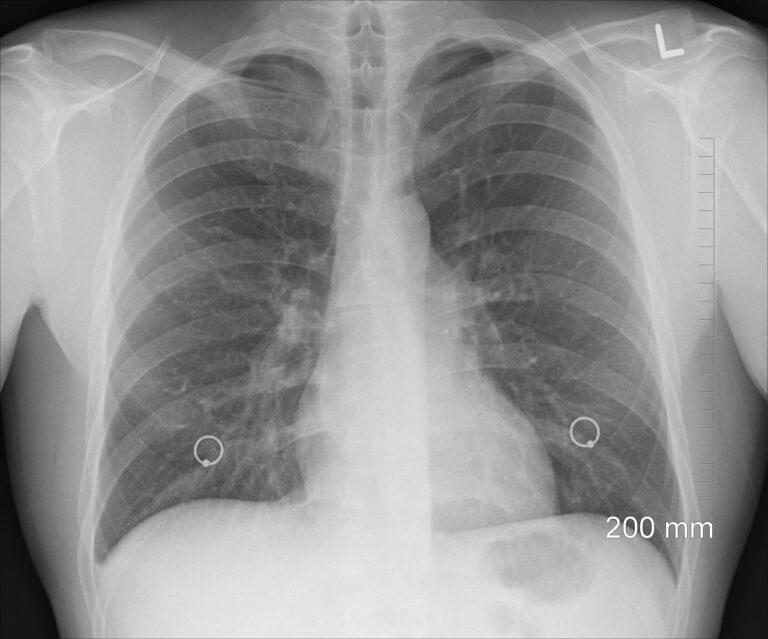

Can You Beat Lung Cancer Without Chemo? The Truth Behind Alternative Treatments

When faced with a lung cancer diagnosis, the first thing many people think about is chemotherapy. It’s the treatment we know best, but it’s also the one that brings with…